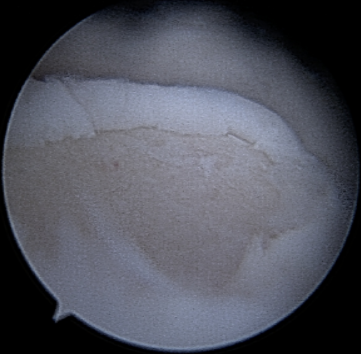

Cartilage injuries in the ankle and foot can be caused by trauma or wear and tear, leading to pain, swelling, and functional limitation.

- Surgery: Arthroscopy (repairs damaged cartilage).